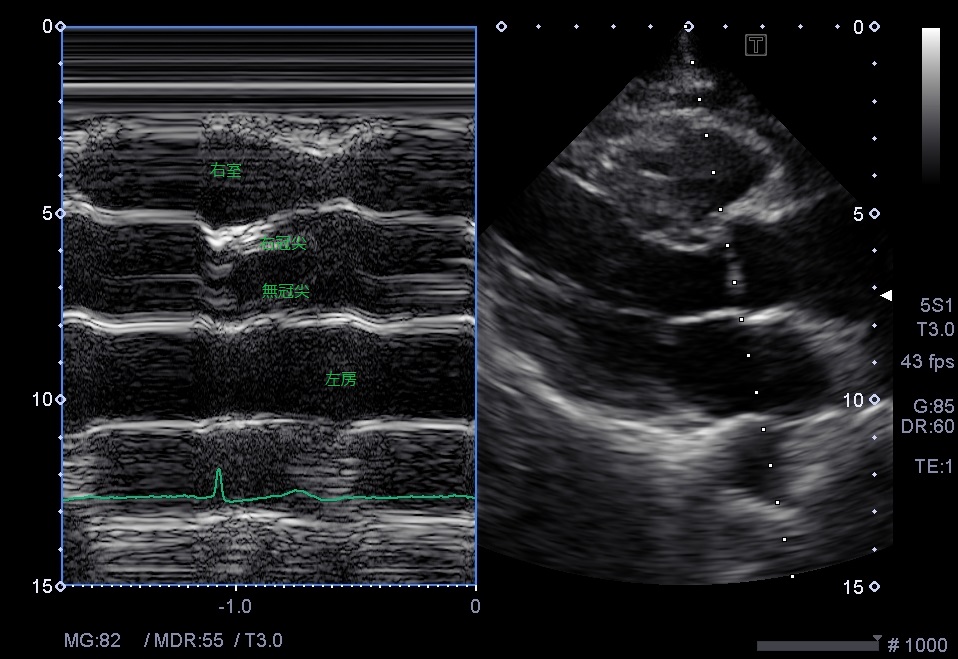

②

右室と左房がやや大きく見える。

右心系が大きく見えるときは、若い人・甲状腺機能更新・妊娠・先天性心疾患etc

下大静脈の拡張がないか、呼吸性変動があるか確認する。

TRがどれくらいか確認する。